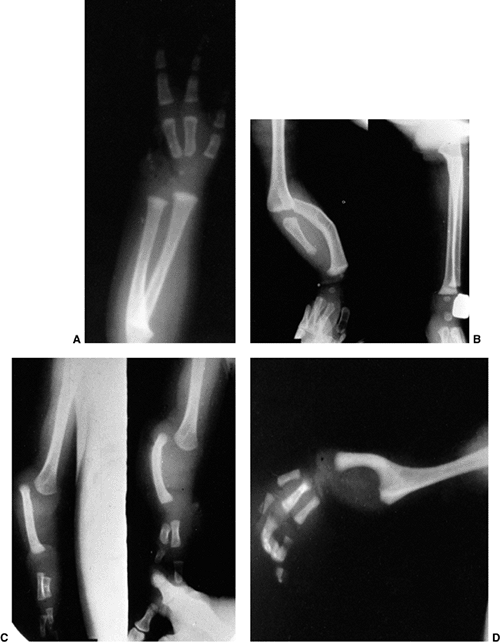

differentiation of parts with skeletal involvement. In this section,

a rare malformation of the upper limb. It is caused by a failure of the

synostosis show anatomic variations from minor radial head deformities

absence of the radial head in patients with no rotation (105) (Fig. 23.8).

The more extensive synostoses are usually fixed in more pronounced

pronation. Plain radiographic classifications have distinguished

partial and complete synostoses. In the partial synostosis there is

often a rudimentary radial head present, but it is posteriorly or

posterolaterally subluxated. In the complete synostosis the radial head

is absent, and the proximal radius and ulna are a single bony mass.

There is always an increased anterior bow of the radius. On occasion,

the synostosis can extend into the middiaphysis of the forearm.